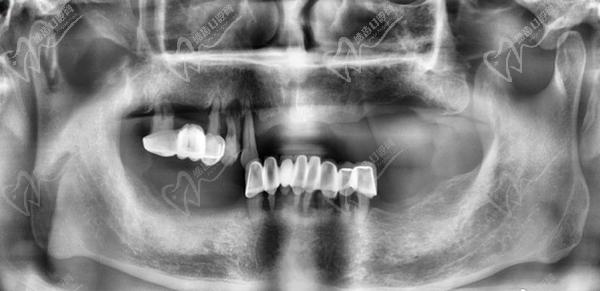

1、術(shù)前檢查和評估:進(jìn)行X光片、CT等影像學(xué)檢查,以確定患者的牙槽骨質(zhì)量和數(shù)量,為手術(shù)方案的指定提供數(shù)據(jù)支持。一般家里的老人患有基礎(chǔ)疾病的只要身體健康、口腔條件達(dá)標(biāo)都可以做,對全口牙齒重度松動的中青年患者亟需修復(fù)的可以做。

重度牙周炎會導(dǎo)致牙齒松動、脫落和牙槽骨的破壞。全口即拔即種種植牙適用于牙周炎患者,可以在一次手術(shù)中同時(shí)拔除松動的牙齒并植入種植體。在手術(shù)前,需要進(jìn)行詳細(xì)的口腔檢查和評估,包括X光片、CT等影像學(xué)檢查,以確定患者的牙槽骨質(zhì)量和數(shù)量。在手術(shù)中,局部麻醉后拔除松動的牙齒,然后在拔牙后的創(chuàng)口內(nèi)植入種植體,并進(jìn)行縫合。術(shù)后需要指導(dǎo)患者進(jìn)行日常護(hù)理和藥物治療,確保創(chuàng)口愈合良好。

牙友1、前天結(jié)束的全口種植牙,拔牙加同期種12顆瑞士士卓曼,即刻負(fù)重!全口牙周炎伴隨多顆牙松動且骨量不足等問題,普通的種植手術(shù)無法滿足生活需求,想要做即拔即種即刻戴上臨時(shí)牙,因?yàn)槌R?guī)的植骨手術(shù)需要等待很長時(shí)間。經(jīng)過正規(guī)醫(yī)院骨質(zhì)評估分析,上頜AO4+兩邊穿翼手術(shù),患者手術(shù)結(jié)束當(dāng)天就可以正常用牙,本人表示非常高興和滿意!感謝醫(yī)院團(tuán)隊(duì)協(xié)作!